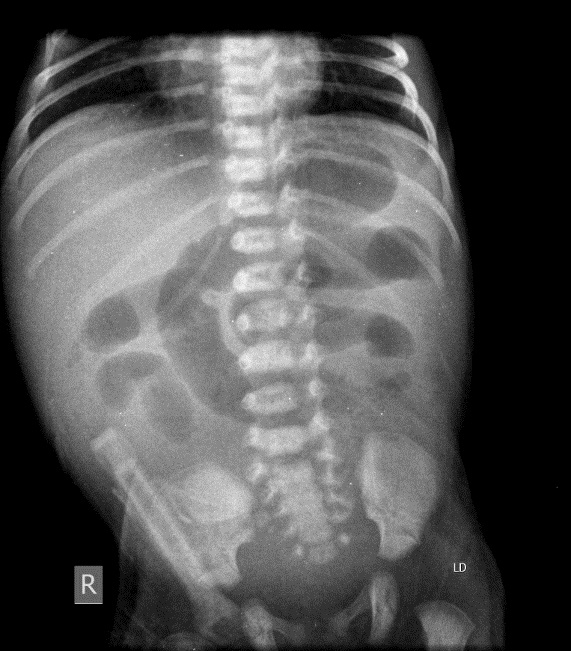

A preterm male born at 35 weeks +5 days of gestation by spontaneous vaginal delivery to a Para 4+ mother. The baby remained well after birth and had physiological jaundice that improved gradually, and baby was discharged home on day 3. On day 7, the baby was brought to the Pediatric emergency department with a history of greenish vomiting. He had five episodes of bilious vomiting, also witnessed on arrival in the emergency department. On presentation, his weight was 2.1 kg; he was active and crying, afebrile, and withoutany respiratory distress. The abdomen was distended, with generalized tenderness. Baby had normal inflammatory markers including leukocyte count and CRP. Abdominal x-ray showed dilated small bowel suggestive of intestinal obstruction with no free gas in the abdomen (Fig. 1). Abdominal Ultrasound showed only excessive gases in the epigastric area.

Figure 1

Xray abdomen showing features of small intestinal obstruction